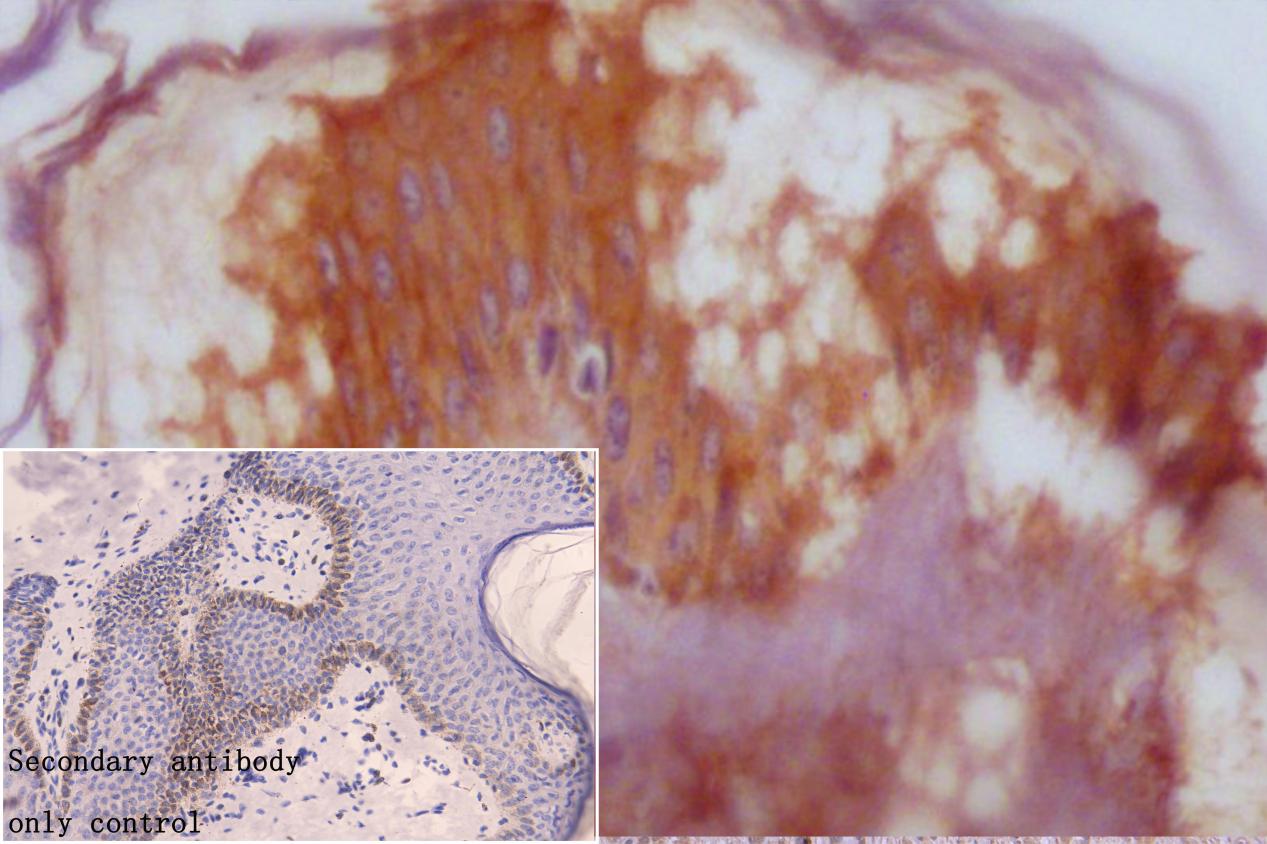

IHC image of CSB-PA866221DSR2HU diluted at 1:50 and staining in paraffin-embedded human skin tissue performed on a Leica BondTM system. After dewaxing and hydration, antigen retrieval was mediated by high pressure in a citrate buffer (pH 6.0). Section was blocked with 10% normal goat serum 30min at RT. Then primary antibody (1% BSA) was incubated at 4°C overnight. The primary is detected by a Goat anti-rabbit polymer IgG labeled by HRP and visualized using 0.05% DAB. Secondary antibody only control: uses 1% BSA instead of primary antibody